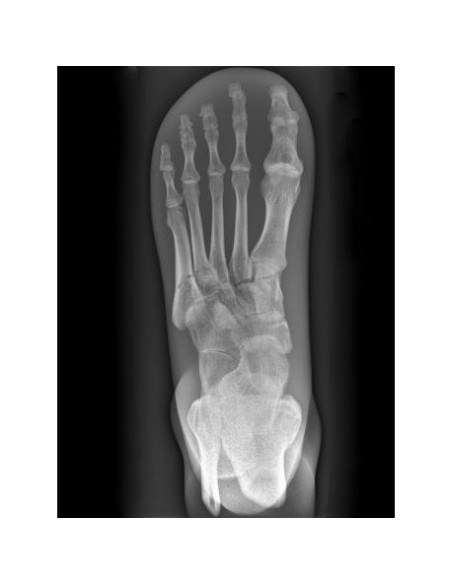

Dieser unentbehrliche medizinische Radiologie-Simulator bietet die einzigartige Möglichkeit, immer wieder Röntgenbilder von einzelnen Körperteilen anzufertigen.

Die Simulationspuppe enthält echte menschliche Knochen und ermöglicht es Ihnen, echte Röntgenbilder zu machen.

Die Knochen sind in Kunststoff eingebettet, der mit einer undurchsichtigen Farbe beschichtet ist, um die inneren Strukturen zu verbergen.

Der radiologische Fußsimulator ist ein handgefertigtes Unikat.

Er kann in Farbe und Form variieren.

Aufgrund der hohen Technologie, die bei der Herstellung verwendet wird, kann es im Inneren zu Verfärbungen und Rissen kommen.

Dies hängt mit der Produktion und nicht mit mangelnder Qualität zusammen